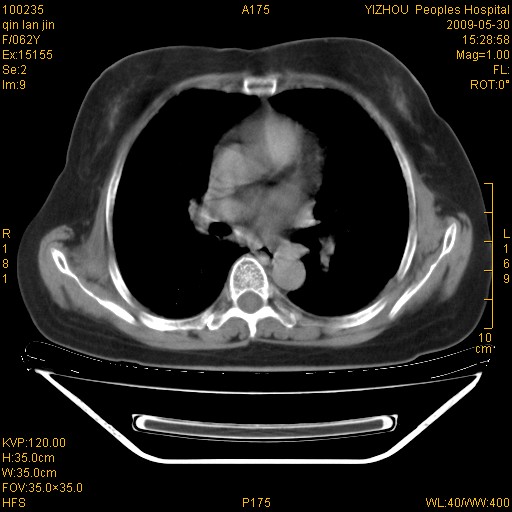

标题: CT20268:肺泡癌?间质性肺炎? [打印本页]

标题: CT20268:肺泡癌?间质性肺炎?

女,62岁,近二年经常咳嗽,近二个月,消瘦、乏力。

纵隔淋巴结大,须排外癌性淋巴管炎